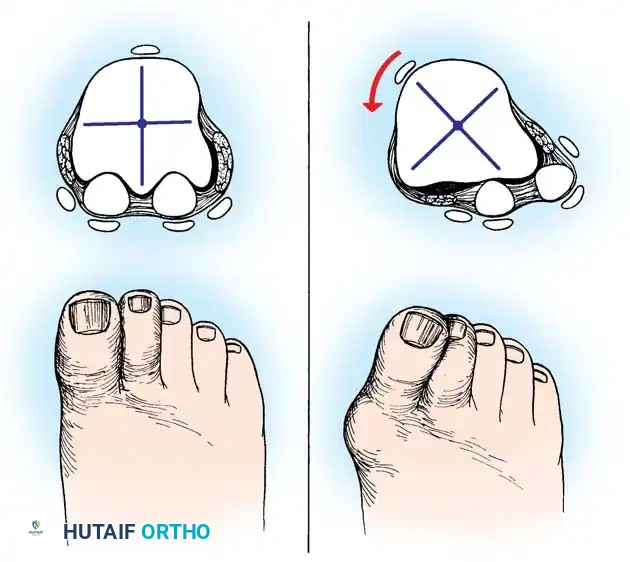

Hallux valgus (lateral deviation of the great toe) is not a single disorder, as the name implies, but a complex deformity of the fi rst ray that frequently is accompanied by deformity and symptoms in the lesser toes (Fig. 78-1). Often the angle between the fi rst and second metatarsals is more than the 8 to 9 degrees usually considered to be the upper limits of normal. The valgus angle of the fi rst metatarsophalangeal joint also is more than the 15 to 20 degrees considered to be the upper limits of normal (Fig. 78-2). If the valgus angle of the fi rst metatarsophalangeal joint exceeds 30 to 35 degrees, pronation of the great toe usually results. With this abnormal rotation, the abductor hallucis, which is normally plantar to the fl exion-extension axis of the fi rst metatarsophalangeal joint, moves further plantarward (Fig. 78-3). In this case, the only restraining medial structure is the medial capsular ligament with its capsulosesamoid portion (inserting into the base of the proximal phalanx) (Fig. 78-4) and capsulophalangeal portion (inserting into the plantar plate). The adductor hallucis, which is unopposed by the abductor hallucis, pulls the great toe further into valgus, stretching the medial capsular ligament (particularly the capsulosesamoid), attenuating this structure, and allowing the metatarsal head to drift medially from the sesamoids. In addition, the fl exor hallucis brevis, fl exor hallucis longus, adductor hallucis, and extensor hallucis longus increase the valgus moment at the metatarsophalangeal joint, further deforming the fi rst ray. The deep transverse intermetatarsal ligament runs between the plantar plates at the metatarsophalangeal joints and does not insert into bone on the adjacent sides of the metatarsal heads. Finally, the sesamoid ridge on the plantar surface of the fi rst metatarsal head (the crista) fl attens because of pressure (abutment) from the tibial sesamoid (Fig. 78-5). With this restraint lost, the fi bular sesamoid displaces partially or completely into the fi rst intermetatarsal space (see Fig. 78-2). In this situation, the patient is bearing less weight on the fi rst ray and more on the lesser metatarsal heads, increasing the likelihood of transfer metatarsalgia, callosities, and stress fracture of a lesser metatarsal.

Fig. 78-3 Pronation of hallux. A, Normal. B, Note plantar shift of abductor hallucis and lateral shift of sesamoids with associated intrinsic muscles of hallux. (Redrawn from Miller J: Acquired hallux varus a preventable and correctable disorder, J Bone Joint Surg 57A:183, 1975.)